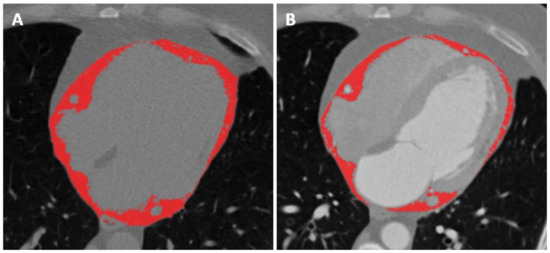

2.3. Image Analysis